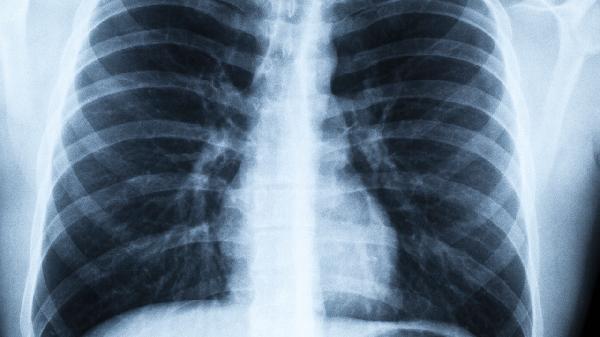

3、针对性影像学

根据初步检查结果,可能需要做肺部CT或全身骨扫描进一步确诊。